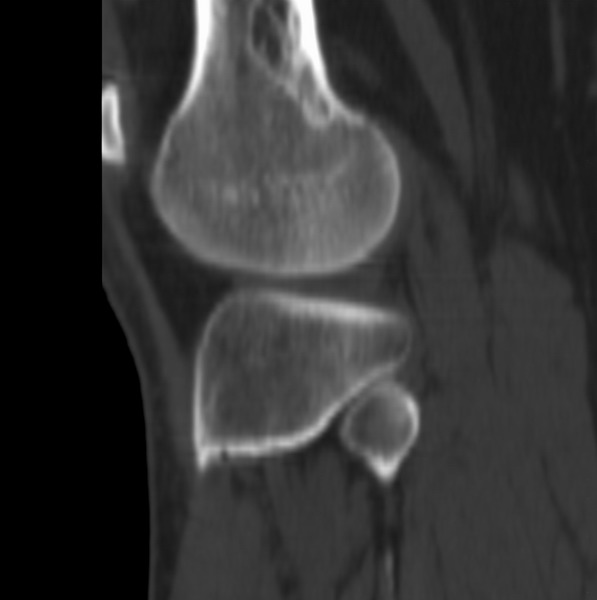

右侧膝关节疼痛一月

男、48

股骨下段、胫骨上段。

1、股骨干骺端病变考虑干骺端纤维性皮质缺损愈后(非骨化性纤维瘤)改变,胫骨近端内生骨瘤(或干骺端纤维性皮质缺损愈后改变);

2、骨关节炎,骨质增生,股骨外侧髁退变性囊肿(关节面软骨下囊肿);

1、股骨干骺端病变考虑干骺端纤维性皮质缺损愈后(非骨化性纤维瘤)改变,胫骨近端内生骨瘤;